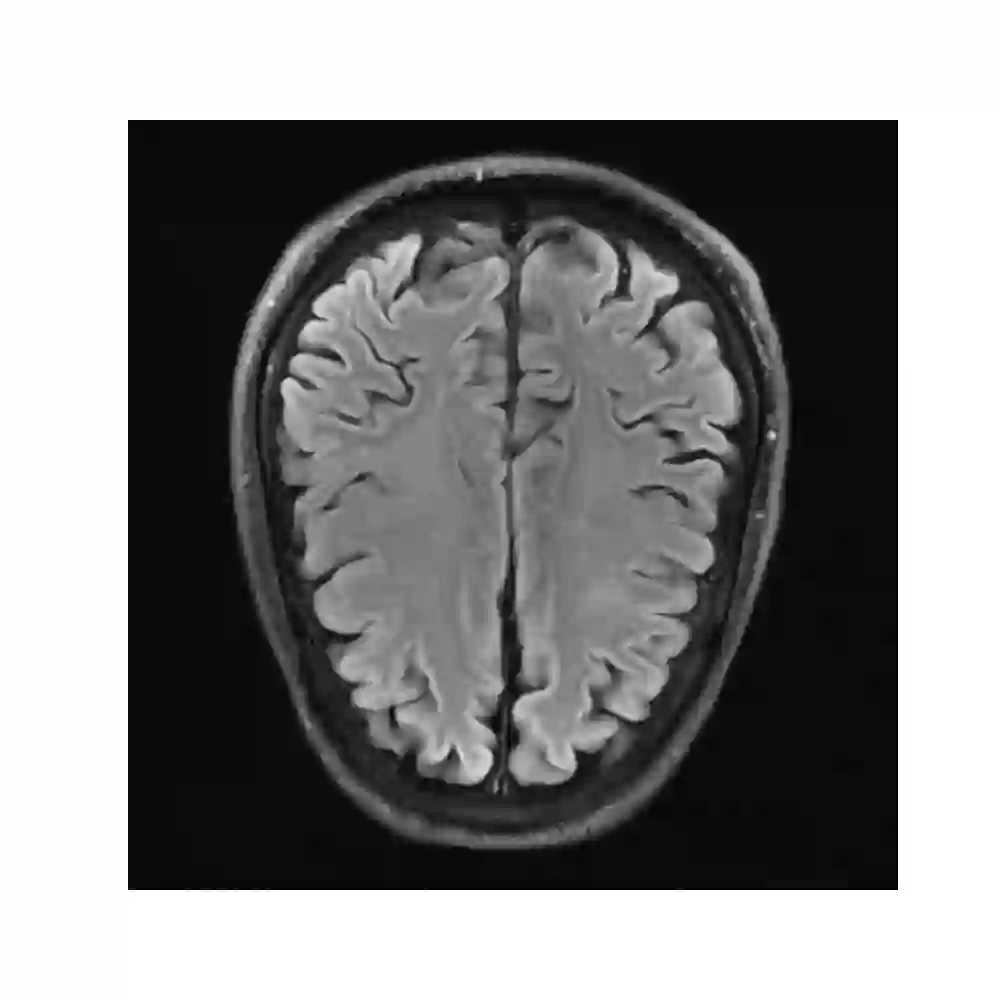

In spite of its extensive adaptation in almost every medical diagnostic and examinatorial application, Magnetic Resonance Imaging (MRI) is still a slow imaging modality which limits its use for dynamic imaging. In recent years, Parallel Imaging (PI) and Compressed Sensing (CS) have been utilised to accelerate the MRI acquisition. In clinical settings, subsampling the k-space measurements during scanning time using Cartesian trajectories, such as rectilinear sampling, is currently the most conventional CS approach applied which, however, is prone to producing aliased reconstructions. With the advent of the involvement of Deep Learning (DL) in accelerating the MRI, reconstructing faithful images from subsampled data became increasingly promising. Retrospectively applying a subsampling mask onto the k-space data is a way of simulating the accelerated acquisition of k-space data in real clinical setting. In this paper we compare and provide a review for the effect of applying either rectilinear or radial retrospective subsampling on the quality of the reconstructions outputted by trained deep neural networks. With the same choice of hyper-parameters, we train and evaluate two distinct Recurrent Inference Machines (RIMs), one for each type of subsampling. The qualitative and quantitative results of our experiments indicate that the model trained on data with radial subsampling attains higher performance and learns to estimate reconstructions with higher fidelity paving the way for other DL approaches to involve radial subsampling.